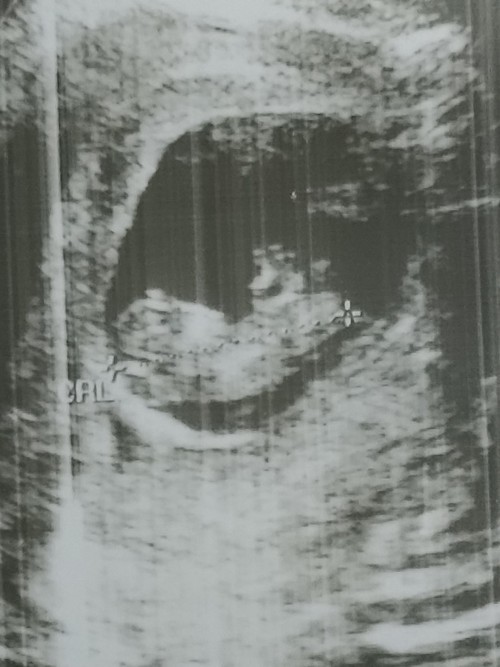

ซาวตอน 9/6 แต่วันนี้ 10 พอดี

Post reply image

ขยับแขนขยับขาแล้วค่ะ❤️